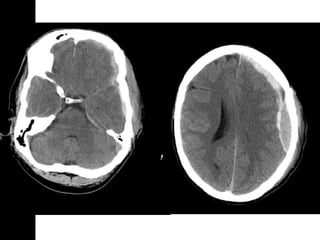

SUBDURAL HEMATOMASUBDURAL HEMATOMA

Occurs between the dura and arachnoid

Can cross the sutures but not the dural

reflections

Due to disruption of the bridging cortical

veins

Hypodense(hyperacute, chronic),

isodense(subacute), hyperdense(acute)

W=33 L=41

SUBDURAL HEMATOMASUBDURAL HEMATOMA Occursbetween the dura and arachnoid Can cross the sutures but not the dural reflections Due to disruption of the bridging cortical veins Hypodense(hyperacute, chronic), isodense(subacute), hyperdense(acute)